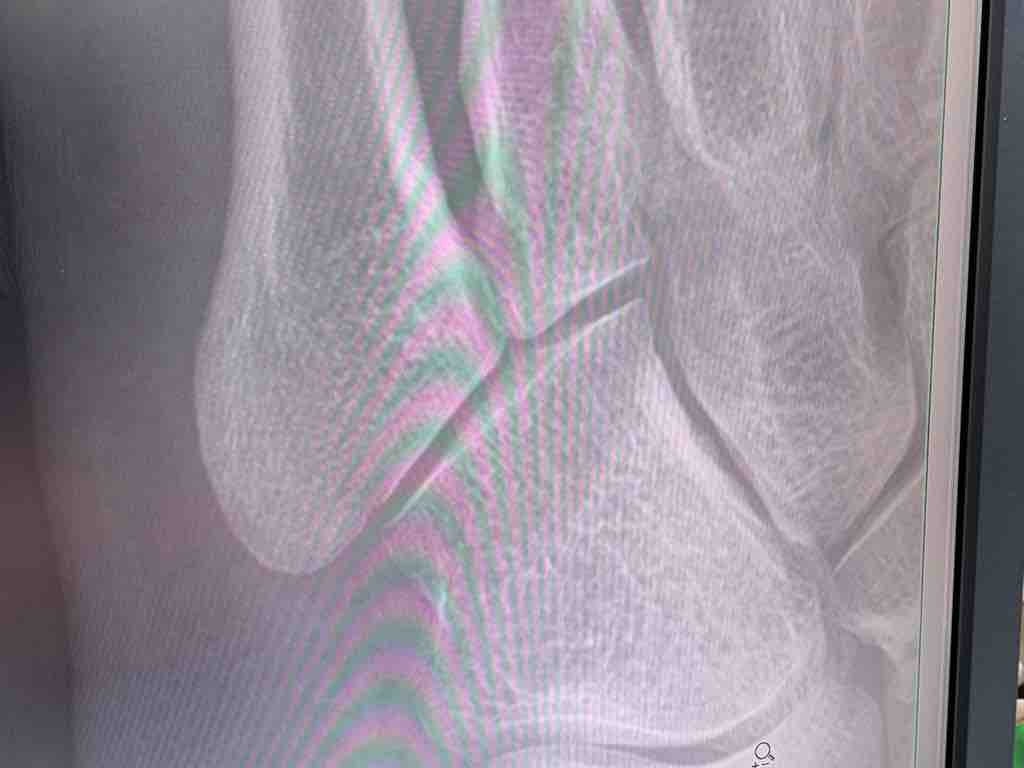

レントゲンを撮影して先生に診てもらいました。

先生 「骨に異常無いからシップ貼って炎症を抑えるんだね」

先生 「レントゲンには写らないけど小指の付け根から出てる腱が炎症起こしてる感じだから使いすぎだろうね」

レントゲンを撮影して先生に診てもらいました。先生 「骨に異常無いからシップ貼って炎症を抑えるんだね」